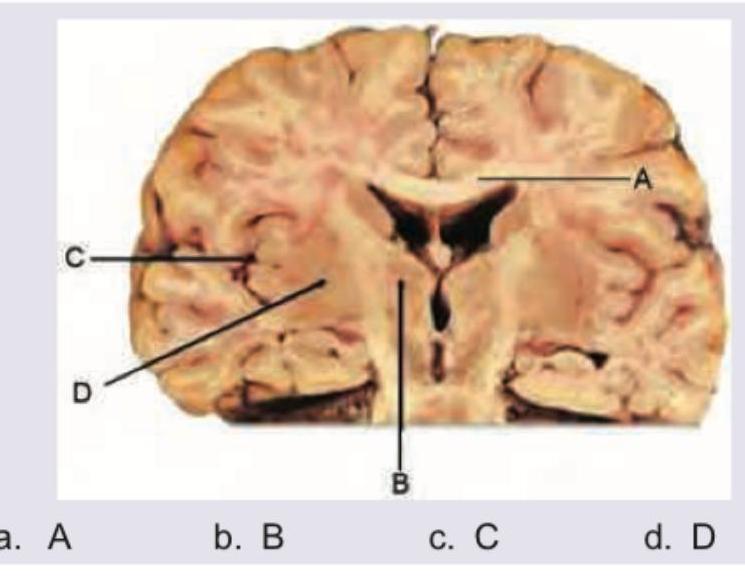

Which of the following depicts insula in the cross section of the brain?

Explanation: ***C*** - The image illustrates a **coronal section of the brain**. The letter C points to the **insula**, a cortical region buried deep within the lateral sulcus, covered by the opercula of the frontal, parietal, and temporal lobes. - The insula is involved in various functions including **consciousness**, emotion, homeostasis, and perception (e.g., taste, pain). *A* - The letter A indicates the **corpus callosum**, a large bundle of nerve fibers connecting the two cerebral hemispheres. - Its primary function is to integrate motor, sensory, and cognitive performances between the cerebral cortex on one side of the brain to the same region on the other side. *B* - The letter B points to the **third ventricle**, a narrow, C-shaped cavity filled with cerebrospinal fluid (CSF) that lies in the midline of the brain, between the two thalami. - It plays a crucial role in the production and circulation of **CSF**, which cushions the brain and spinal cord. *D* - The letter D is pointing to the **putamen**, which is part of the basal ganglia. - The putamen is involved in **motor control** and learning, particularly in the regulation of voluntary movement.